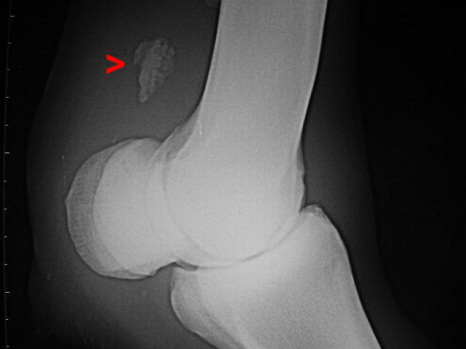

Verkalkung im Fesselträger